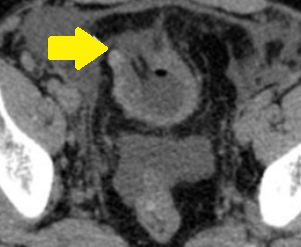

Αξονική τομογραφία οπισθοπεριτοναίου. Κίτρινα βέλη – Αμφοτερόπλευρη διάταση ουρητήρων. Ευγενική παραχώρηση Dr. V. Penopoulos.